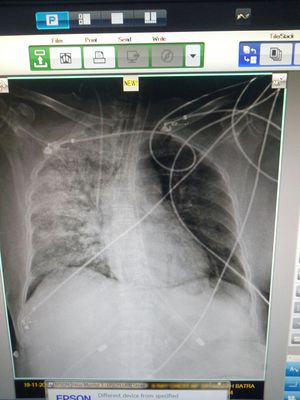

Sp02 is 92℅ on ventilator , weight is 50 kg , select a mode of ventilation and settings